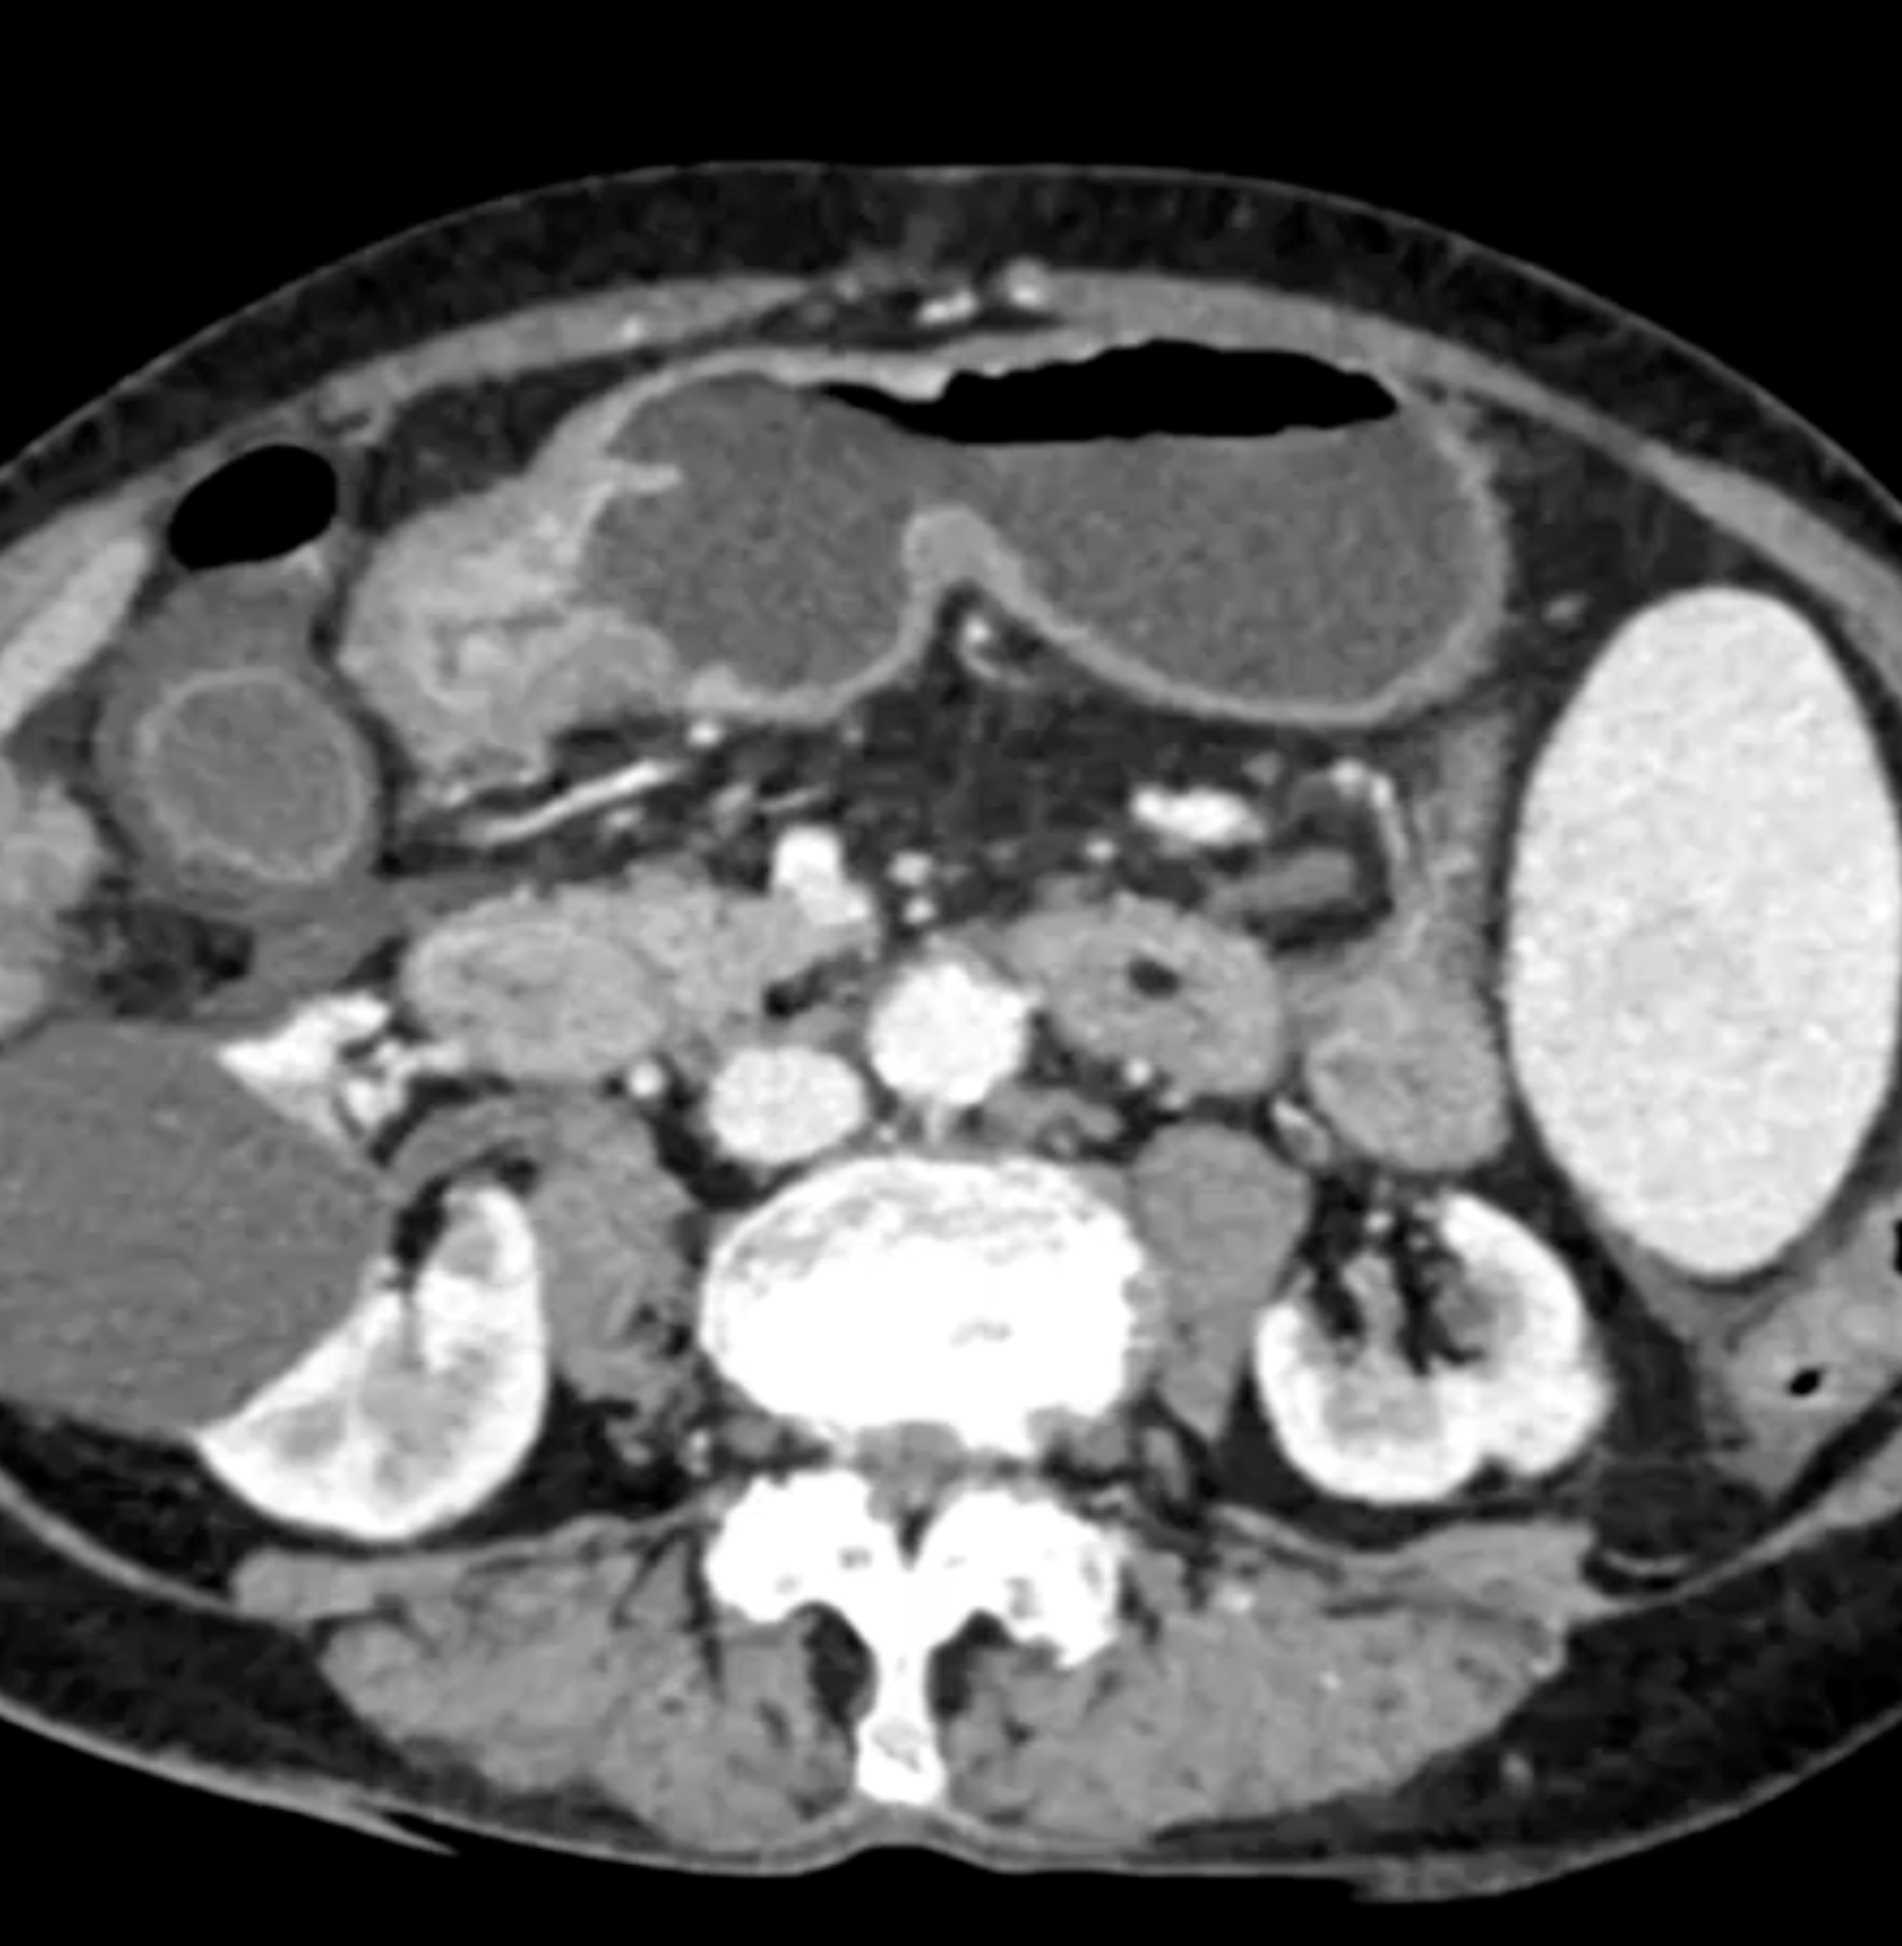

Watermelon Stomach (Gastric Antral Vascular Ectasis)